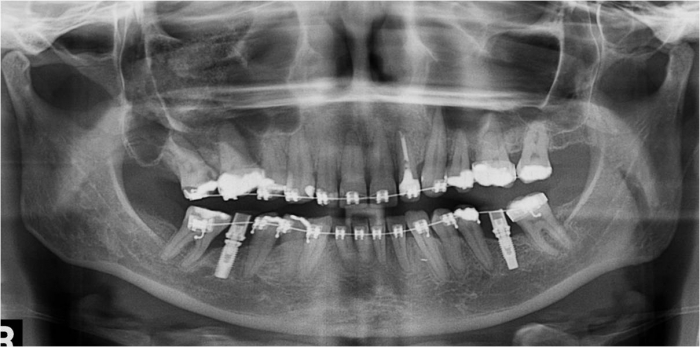

Raio x inicial